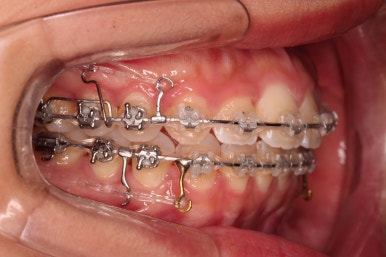

8개월째 사진입니다.

이제 약 4~5개월의 시간만 남았을 뿐입니다.

분명 처음보다는 좋아지고는 있으나 많이 아쉽습니다.

여기서 약간의 변화만 생기고 종료할 수 밖에 없다면,(물론 모두 수용하기로 하고 시작하였고, 환자분은 만족하실 수 있겠지만) 매우 아쉬움이 큰 치료였을 법 합니다.

일단 무조건 당깁니다.

1, 2, 3단계고 뭐고 디테일한 마무리고 뭐고 전부 동시에 진행합니다.

당기기-마무리 같이 진행하면서 할 수 있는 최선을 다해 뒤로 당겨줍니다.